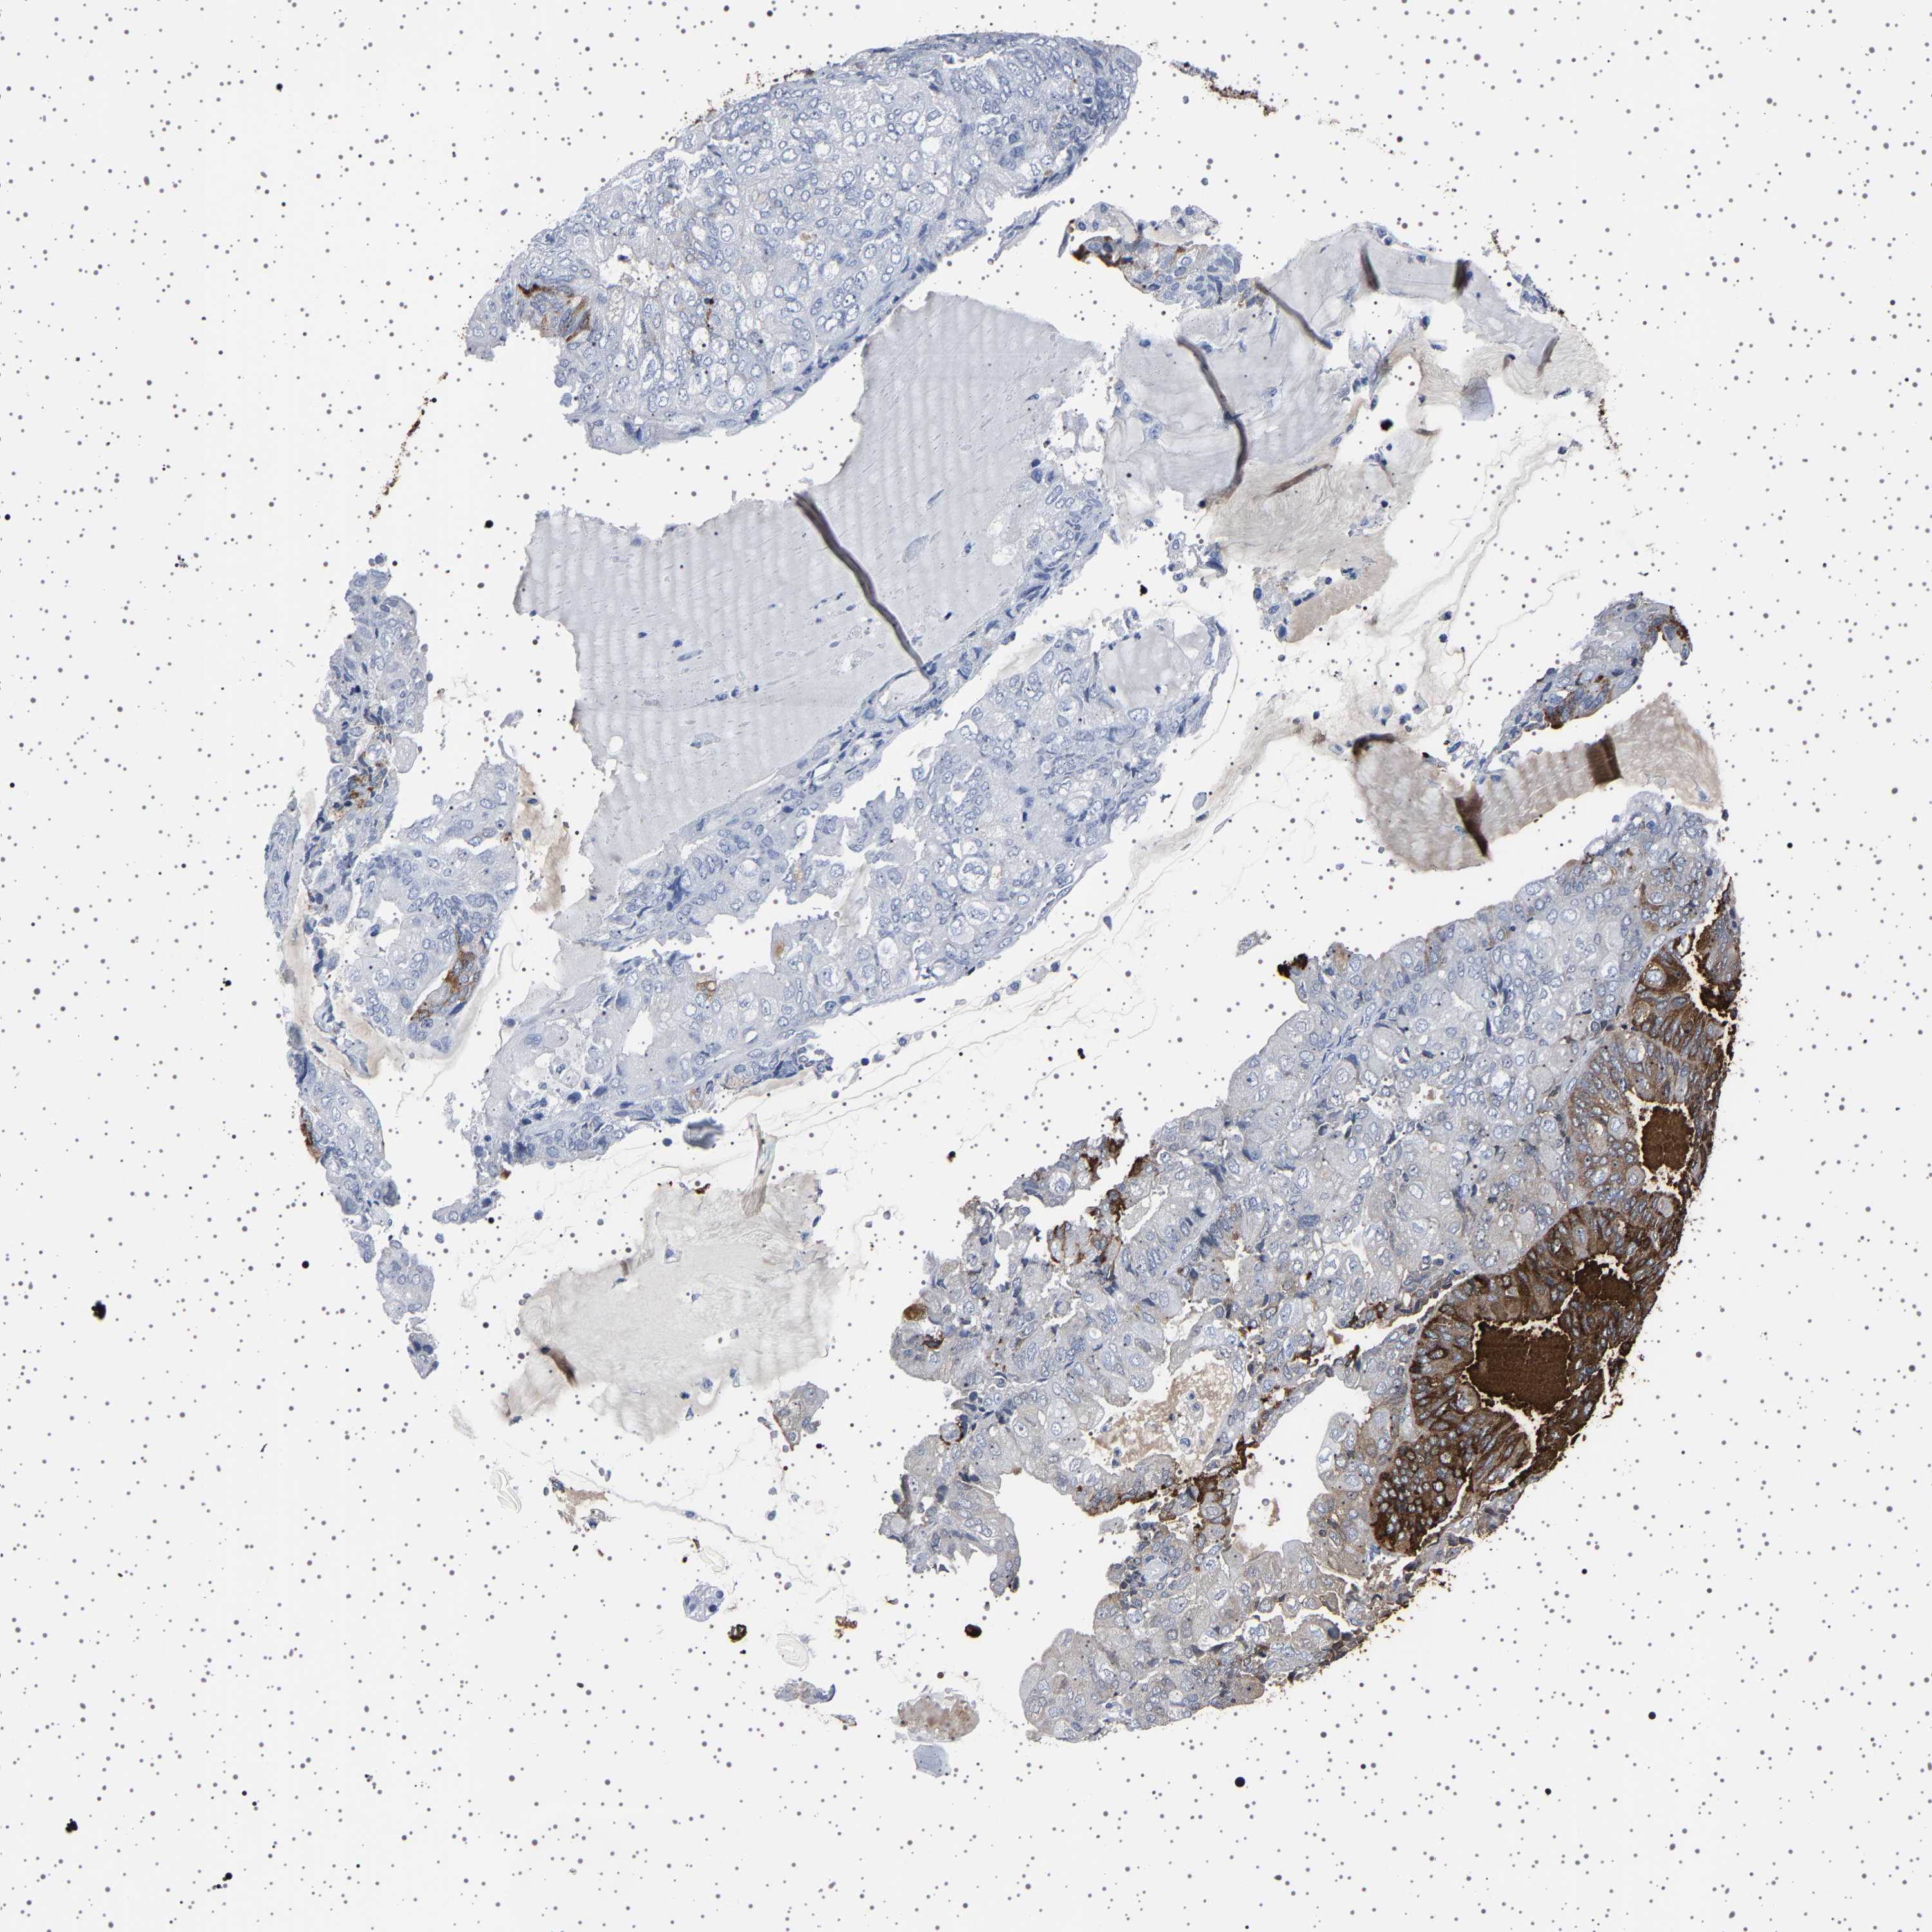

ENDOMETRIAL CANCER - Protein expressioni

A mouse-over function shows sample information and annotation data. Click on an image to view it in a full screen mode. Samples can be filtered based on level of antibody staining by selecting one or several of the following categories: high, medium, low and not detected. The assay and annotation is described here.

Note that samples used for immunohistochemistry by the Human Protein Atlas do not correspond to samples in the TCGA dataset.

Antibody stainingi

Antibody staining in the annotated cell types in the current human tissue is reported as not detected, low, medium, or high, based on conventional immunohistochemistry profiling in selected tissues. This score is based on the combination of the staining intensity and fraction of stained cells.

Each image is clickable and will lead to virtual microscopy that enables deeper exploration of all samples and also displays staining intensity scores, fraction scores and subcellular localization as well as patient and tissue information for each sample.

Antibody HPA035464

Antibody CAB020681

Staining

High

Medium

Low

Not detected

Intensity

Strong

Moderate

Weak

Negative

Quantity

>75%

75%-25%

<25%

None

Location

Nuclear

Cytoplasmic/membranous

Cytoplasmic/membranous,nuclear

Adenocarcinoma, NOS

Adenocarcinoma, metastatic, NOS

Neoplasm, malignant, NOS